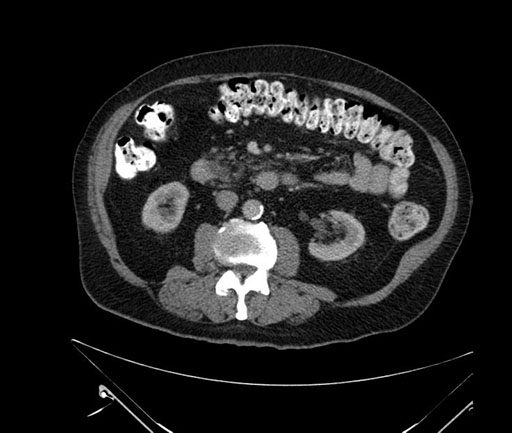

Whipple (pancreaticoduodenectomy) [case 7]

Coronal - stented